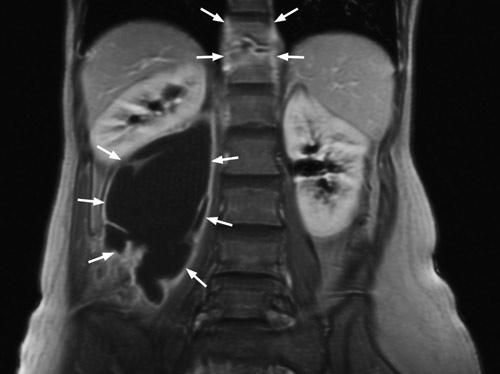

She had an erythrocyte sedimentation rate of 49 mm/h. Other general blood tests, including an HIV test, were normal. Both chest X-ray and urine culture for mycobacteria were negative. MR abdomen revealed findings as for spondylodiscitis at level Th11/Th12 with a large depression abscess in the right m.psoas (left). The abscess measured approximately 14 cm craniocaudally and extended caudally to the level of the L5 corpus vertebrae. A section through the abscess is seen on the right. Microscopy of the abscess material revealed no findings of acid-resistant rods. Culturing and polymerase chain reaction revealed findings of Mycobacterium tuberculosis. About 350 ml pus was drained off and long-term tuberculostatic treatment was started. The woman is being monitored regularly through outpatient follow-up.